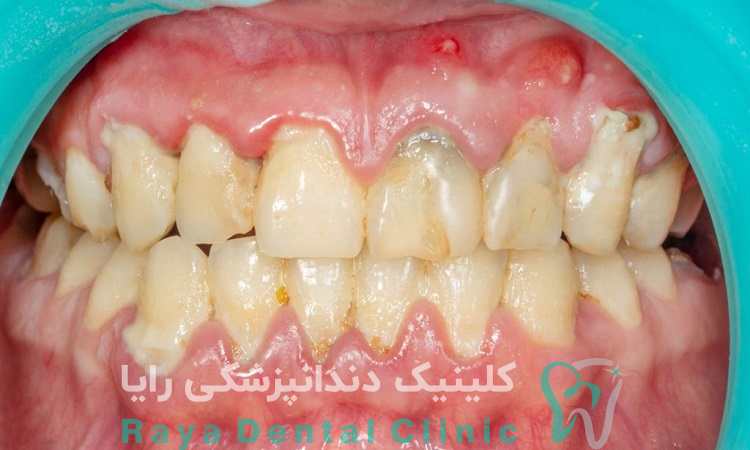

پلاک دندان یک لایه نازک، بی رنگ یا زرد کم رنگ است که به سطح دندان ها و لثه ها می چسبد. این لایه در اثر تجمع باکتری ها و باقی مانده های مواد غذایی ایجاد می شود و به مرور زمان می تواند سطح دندان را زبر کند. اگرچه پلاک در مراحل اولیه به سختی قابل مشاهده است، اما می تواند به مرور باعث تغییر رنگ دندان ها شده و ظاهری زرد یا حتی قهوه ای ایجاد کند.

یکی از علائم رایج پلاک دندان، احساس زبری روی سطح دندان هاست که با لمس زبان به وضوح قابل تشخیص است. همچنین پلاک ممکن است باعث ایجاد بوی بد دهان (هالیتوز) شود، زیرا باکتری های موجود در آن ترکیبات بودار تولید می کنند. در مراحل پیشرفته تر، تجمع پلاک می تواند به حساسیت دندان ها منجر شود که در هنگام مصرف غذاهای سرد یا گرم احساس می شود.

اگر پلاک دندان به موقع تمیز نشود، می تواند به تارتار (جرم دندان) تبدیل شود که سخت تر و مقاوم تر به تمیز کردن است. این وضعیت ممکن است باعث التهاب لثه ها (ژنژیویت) شود که با علائمی چون قرمزی، تورم و خونریزی لثه ها هنگام مسواک زدن همراه است. در مراحل پیشرفته تر، پلاک و جرم دندان می توانند منجر به بیماری های جدی تر لثه مانند پریودنتیت شوند که خطر از دست دادن دندان ها را افزایش می دهد.